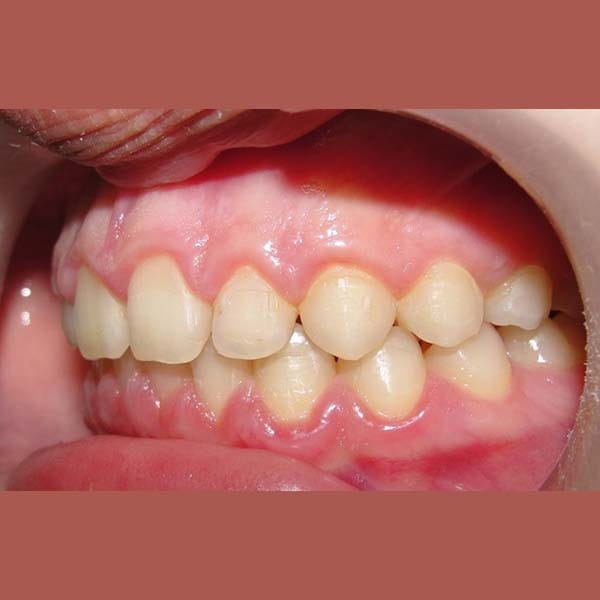

AFTER

A case of severe protrusion in the upper anterior teeth that we treated with Mandibular Anterior Repositioning Appliance at first stage -which is is used to move the lower jaw forward- and then completed the treatment using a conventional orthodontic device.